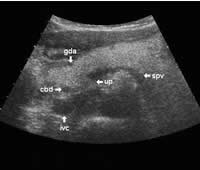

The main bile duct runs from the liver hilum to the right of and above the portal vein into the right dorsal part of the pancreatic head, where it runs vertically into the duodenum. The pancreatic duct typically runs along the body and tail to join the common bile duct near the duodenum. The gastroduodenal artery is sometimes seen in its position along the front margin of the pancreatic head, where it runs in a nearly parallel direction to the common bile duct. Like the common bile duct and pancreatic duct, however, the gastroduodenal artery is not always clearly seen due to its small diameter. The duodenum covers the right and bottom margins of the pancreatic head.

This study shows anatomical landmarks in the bright pancreas of a slightly obese patient:

Transverse planes in caudal direction: